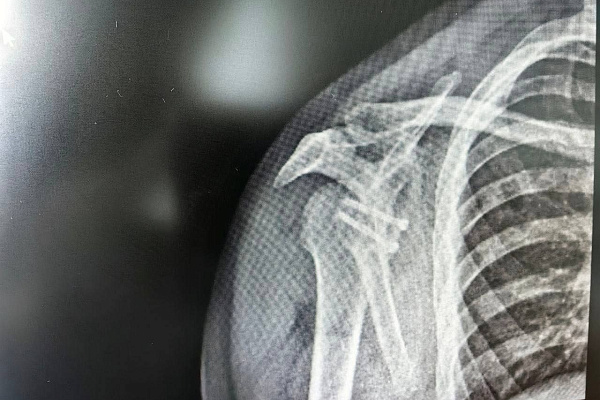

Столкнувшиеся с такой же проблемой друзья по команде уже перенесли операции. Кто-то ездил для этого в Москву, а кто-то - за границу. Данила решил довериться сургутским травматологам-ортопедам. Врачи диагностировали давний разрыв суставной губы и обширный дефект кости. Чтобы стабилизировать сустав, им необходимо было восполнить утраченную костную ткань.

Как раз в этом и заключается суть операции Латарже. Для замещения дефекта используют фрагмент клювовидного отростка лопатки. Вместе с сухожилием его перемещают туда, где образовался костный дефицит, и фиксируют специальными винтами. За счёт транспозиции костного блока появляется дополнительная площадь контакта головки плеча с лопаткой, укрепляется суставной край. Усиливает этот эффект и перенесённое сухожилие. Образовавшаяся сухожильная петля будет препятствовать смещению головки плечевой кости.